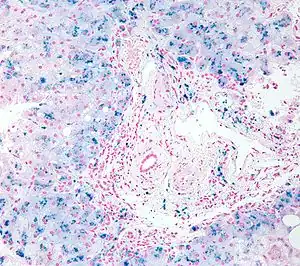

| Micrograph of a liver biopsy showing iron deposits due to iron overload. Iron stain. | |